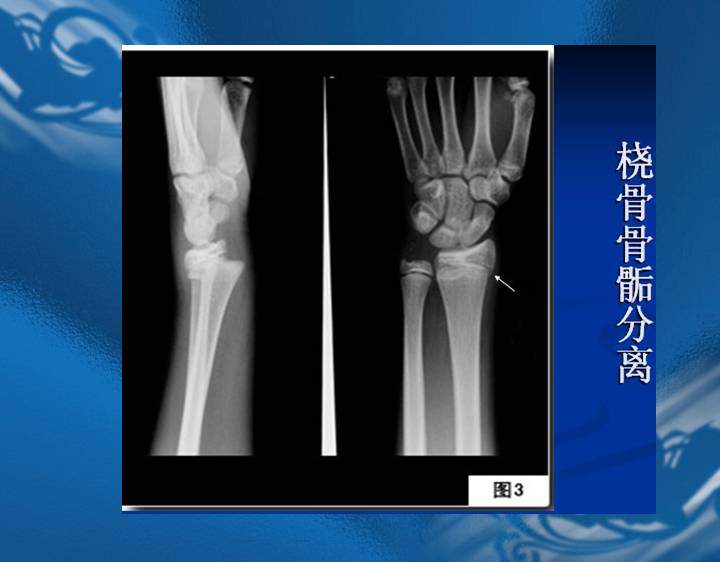

执业医师资格考试“实践技能”影像学辅导资料